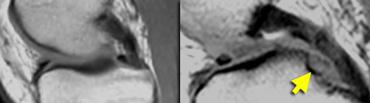

TRÁI: chân bám sụn chêm trong bình thường nằm ngay phía trước dây chằng chéo sau. PHẢI: mất chân bám sừng sau do rách chân bám sụn chêm.

Chân bám sừng sau nằm ngay phía trước dây chằng chéo sau.

Nếu không thấy chân bám này trên các lát cắt sagittal, cần nghĩ đến rách chân bám sụn chêm (hình minh họa).